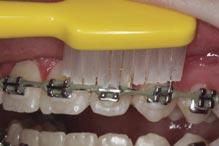

Several studies have investigated the efficacy of manual and electric toothbrushes (Figures 2a and 2b). Some authors have found electric to be more effective than manual models,5 while others could not reproduce these conclusions. Conversely, the opposite has also been demonstrated.6 A recent systematic review and meta-analysis on this topic emphasised the equivocal nature of the current evidence.7 Various manual toothbrush designs have also

been investigated (Figures 3a and 3b). Research has found no significant difference in plaque removal effectiveness between different manual designs.8 There is some evidence that new models of electric toothbrushes may be more effective than traditional ones.

The current consensus is that there is insufficient evidence to advocate for the use of electric over manual toothbrushes, or for any one manual design, for improving plaque control in FA patients. Therefore, the dental team should aim to improve patients’ knowledge and awareness, in conjunction with other aids, rather than focusing on the type of brush used.